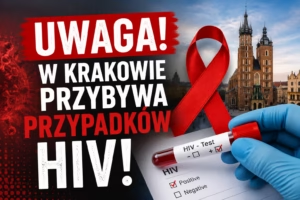

Niepokojące dane napływają z krakowskich szpitali. Lekarze alarmują o wyraźnym wzroście liczby zakażeń HIV oraz przypadków pełnoobjawowego AIDS. Tylko w jednym...